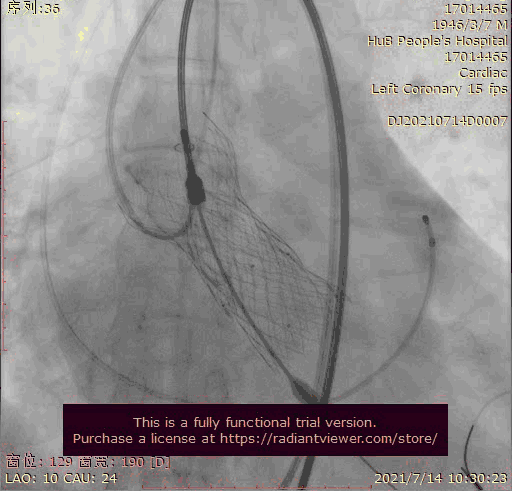

奇思妙想使用射频消融大头压住支架至窦底

在大头压迫支架下释放第二个瓣膜

第二个支架完美释放固定第一个支架

术后基本无返流

3.第三次释放瓣膜后位置的把控非常精准,瓣膜位置合适,但由于稳定性差,撤出输送系统时瓣膜跳至窦上,此时非常凶险,瓣膜无法固定住,受到血流的冲击,可能对升主造成夹层的风险,一般会选择开胸取出,但风险非常,在江洪教授的思考下和团队的讨论下,决定使用射频消融大头穿过支架网孔使瓣膜到窦底固定,在此基础上释放第二个瓣膜,使用第二个瓣膜花冠固定住第一个瓣膜

4.第四次瓣膜释放后两个瓣膜均稳定住,造影超声评估无瓣周漏,二尖瓣反流也基本消失,观察一小时后,无其他情况。患者顺利下台